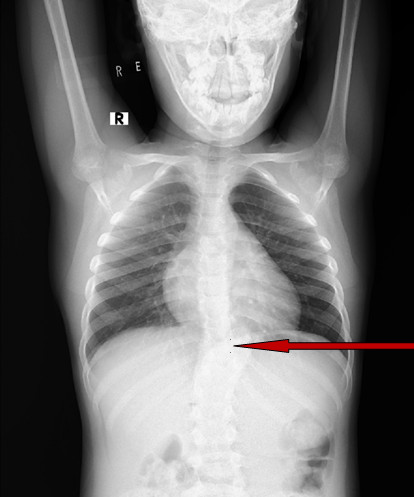

Volver a los detalles del artículo Tuberculosis vertebral